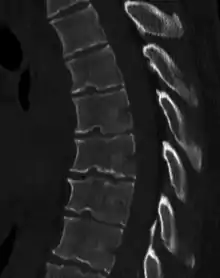

| Scheuermann's disease | |

| Other names | Scheuermann's kyphosis, Calvé disease, idiopathic juvenile kyphosis of the spine |

| Scheuermann's disease on lateral Xray of the T spine | |

Scheuermann's disease is a self-limiting skeletal disorder of childhood. Scheuermann's disease describes a condition where the vertebrae grow unevenly with respect to the sagittal plane; that is, the posterior angle is often greater than the anterior. This uneven growth results in the signature "wedging" shape of the vertebrae, causing kyphosis. It is named after Danish surgeon Holger Scheuermann.[3][4][5]